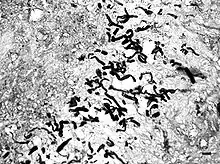

Pythiosis is caused by Pythium insidiosum and occurs most commonly in dogs and horses, but is also found in cats, cattle, and humans. In the United States it is most commonly found in the Gulf states, especially Louisiana, but has been found in midwest and eastern states. It is also found in southeast Asia, eastern Australia, New Zealand, and South America. Pythiosis occurs in areas with mild winters due to the organism surviving in standing water that does not reach freezing temperatures.[2] Pythium occupies swamps in late summer and infects dogs who drink water containing it. The disease is typically found in young, large breed dogs.[1]